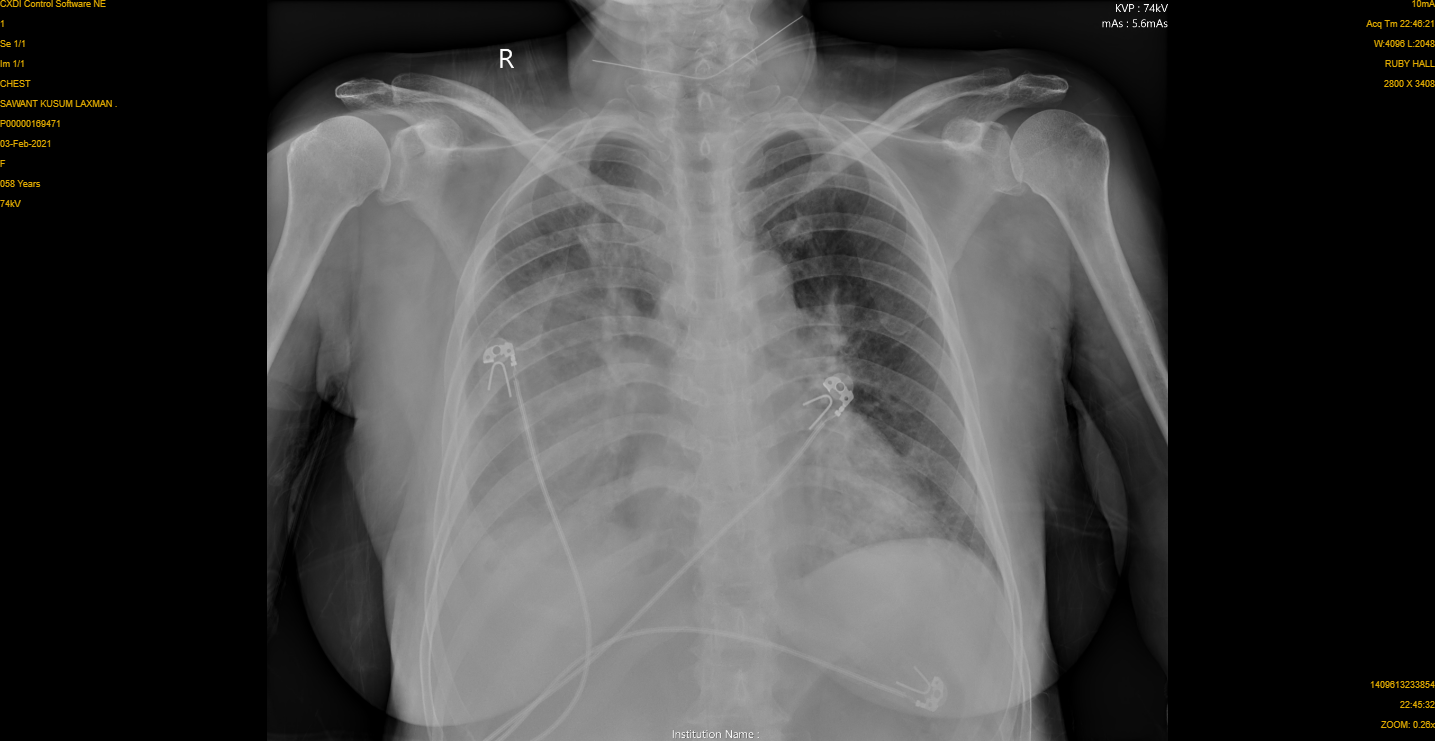

| The Chest Xray shows improvement in opacity and the drain is seen in place |

We managed her with strict control of diabetes via an endocrinologist and drained the pus with help of Pigtail catheter or tube.

Around 550 ml of Pus was drained over a period of four days.